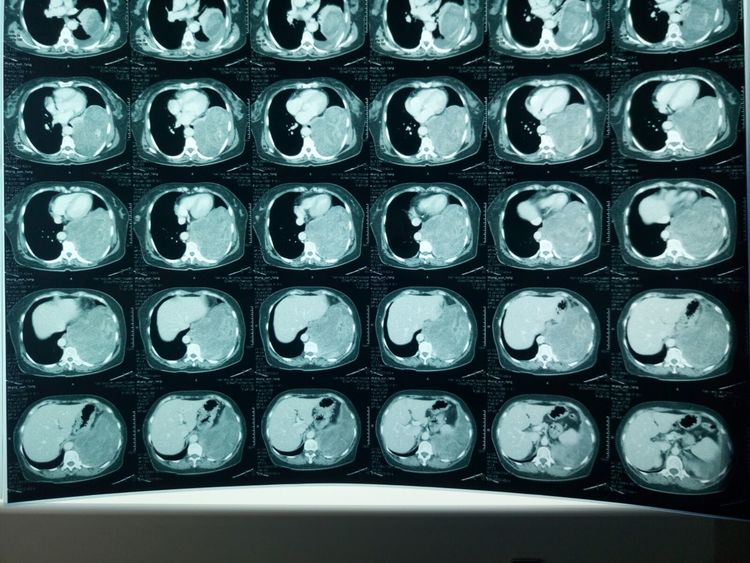

入院胸部ct,提示肿瘤直径约17*15*10cm,占据胸腔一半以上空间。

肿瘤与胸主动脉、下肺静脉等大血管关系密切。